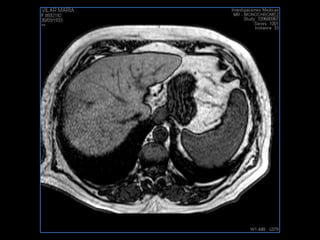

PROTOCOLO abdomen COR T2, AXIAL supresion grasa AX T1 +SAG T2  CON   GADOLINIO :  COR T1+AX T1(DIN) SAT: NO  FASE: RL THK: 6MM  COIL:  GAP: (FACTOR 1.4) 2MM FOV: 40 CM NEX:2 SINCRONIZACION RESPIRATORIA EN 3 O 4 CICLOS ALE

resonancia de abdomen